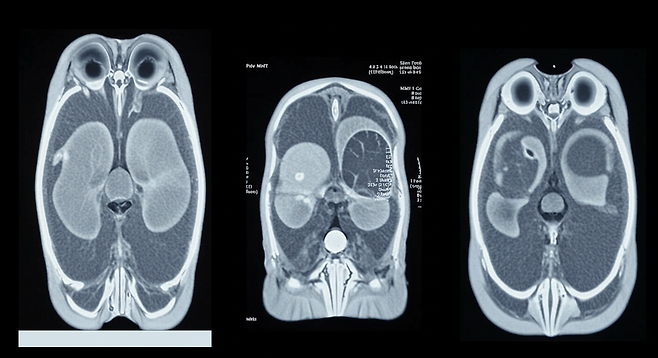

- 초진: 전문의 상담 후 설문지 작성, 코와 목 내시경, 혈액검사, CT, X-ray 검사 진행